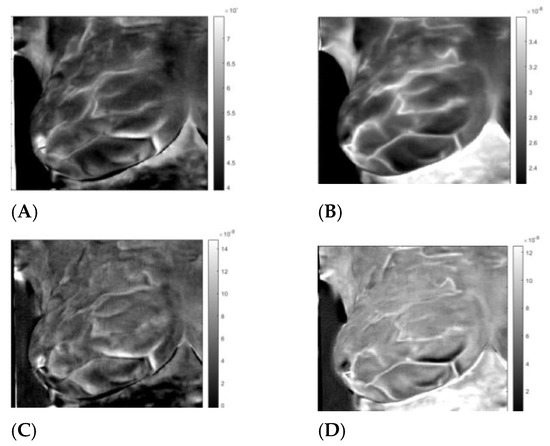

3. Results

3.3. Analysis